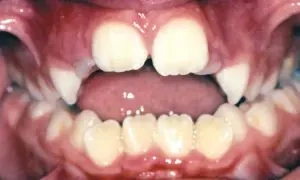

Openbite

Proper chewing is impacted by this type of bite, in which the upper and lower front teeth do not overlap. Openbite may cause a number of unwanted habits, such as tongue thrusting.